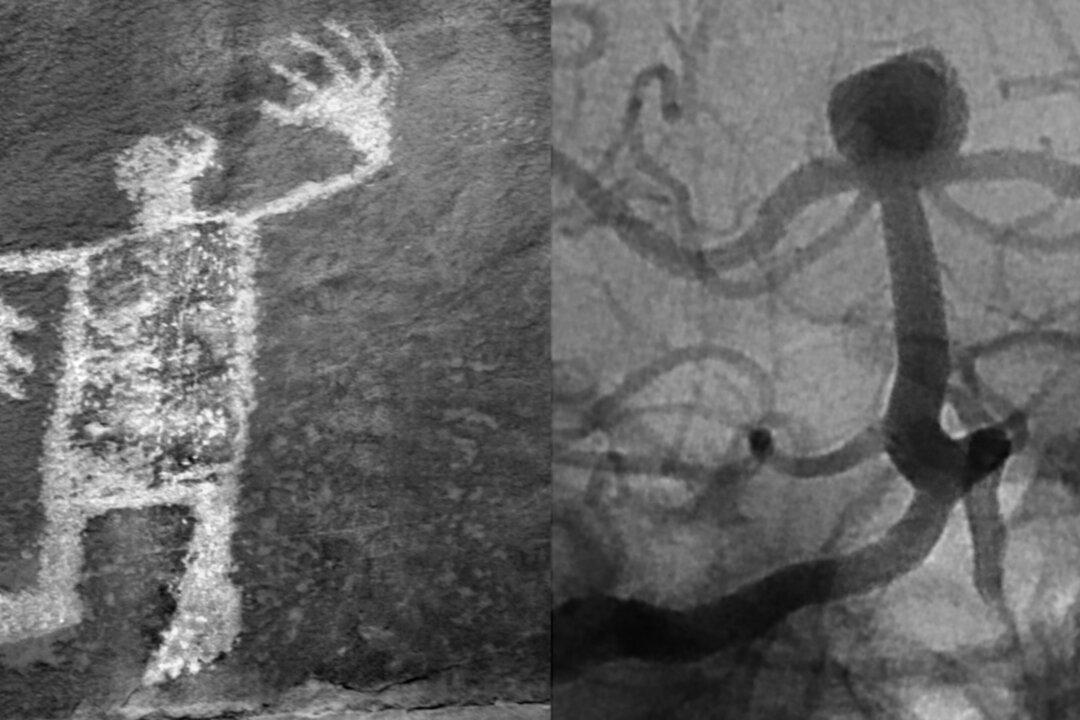

The visionary records of the Anasazi, Hohokam, and other little-known ancient peoples are scattered high on the ledges of rock faces in the American Southwest. Anthropologists have long credited shamans with the ability to see inside and outside, and these rock-face petroglyphs as the records of such visions. One remarkable composition by Tallmadge titled “Petroglyph, Utah/Cerebral Aneurysm, Coiled,” pairs a photograph of a standing-man petroglyph with a multi-armed vertical figure of similar size. Tallmadge’s composition, too, is an inside-outside view.

Each of Tallmadge’s labels tells us exactly what she has photographed. The photograph titled “Aspen, Utah/Lower Limb Angiogram,” for example, presents outlines of jagged tree branches on the left and the bone and muscle of someone’s leg on the right. Similarly, “Tree Branch, Ottawa/Cerebral Angiogram” is composed of two frames with conjoined dark twisting outlines, left and right, lines twisting in seemingly similar ways.

The right side of each pairing, however, is a decidedly privileged view. Each print on the right is a detail from an image made by contemporary medical technology. Most of us have not seen such imagery before. Nonetheless, these are the images our doctors study: the imagery of human bone, vein, and tissue—life forms as seen in CT scans, x-rays, angiograms, and MRIs.